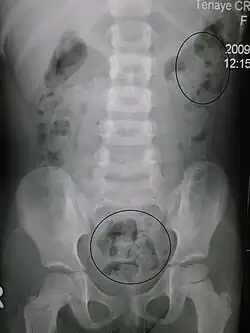

La constipation chez un jeune enfant aperçue par rayon X. | |